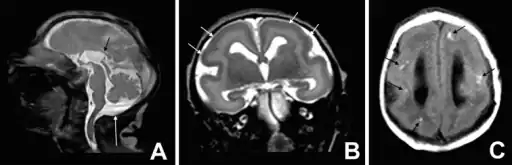

a-c)T1 and T2 image- microlissencephaly -

MRI of a patient with a TUBA1A mutation showing microlissencephaly with cerebellar hypoplasia. a. smooth brain surface (arrow) b. absent corpus callosum (arrow).